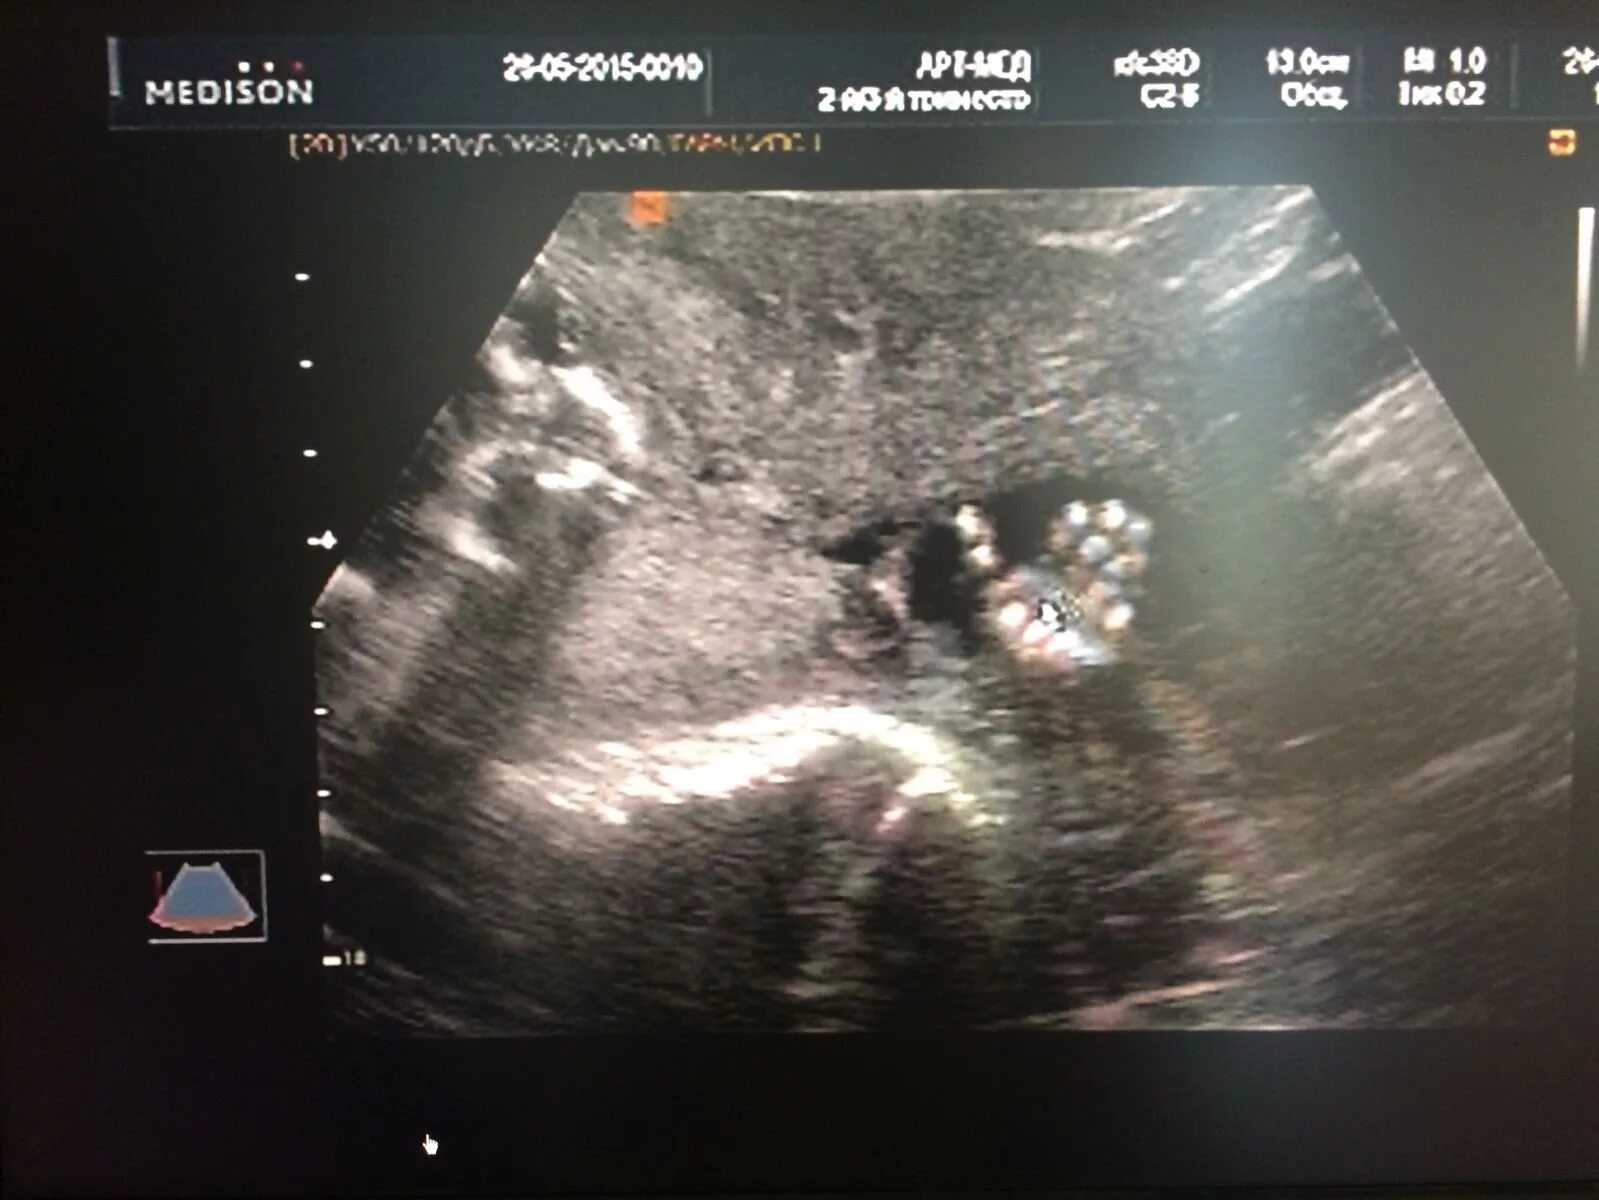

Скрининг 21 неделя